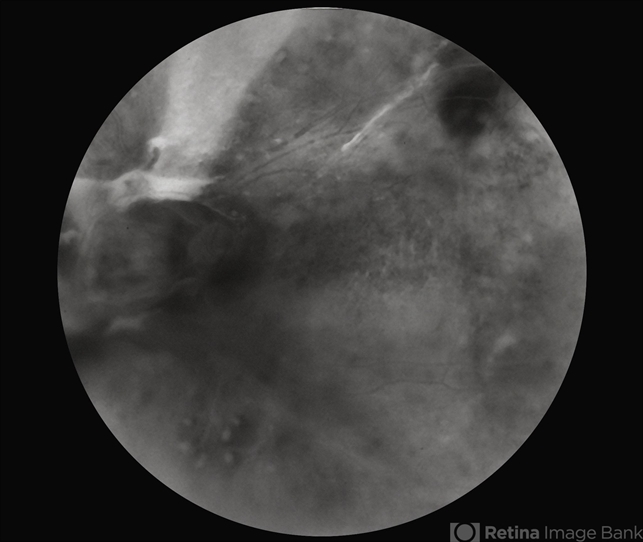

By Alex P. Hunyor, MD By Alex P. Hunyor, MD

Co-author(s): From the slide collection of Dr ABL Hunyor

- Uploaded on Sep 30, 2013.

- Retinal vein occlusion

- central retinal vein occlusion (CRVO), laser treatment

- Fundus camera

- Extensive NVD, NVE and vitreous haemorrhage complicating previoius attempted laser-induced chorioretinal anastomosis for CRVO, left-eye, late fluorescein angiogram.